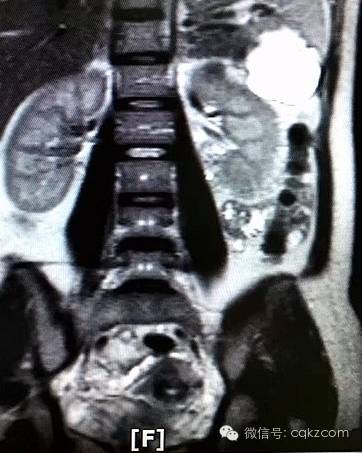

为找出原因,7月12日,王婷更换了一家医院进行检查,并增加了肝胆胰脾肾超声检查项目。正是在脾脏部位,一个活生生的胎儿被发现。当日下午,王婷在家人陪同下来到西南医院就诊,随即被妇产科紧急收治入院。该院妇产科梁志清教授和肝胆科郑树国等知名专家会诊后,建议先使用药物阻止胎儿过快生长,损伤王婷的脾脏,然后通过手术拿掉胎儿,并尽量保留一半脾脏及其功能。

医生翻看类似罕见病例的治疗文献时发现,其他医院都是直接通过开腹手术,整个切除脾脏连同胎儿一并取出。“这样的手术对患者伤害太大了,我们想尽可能不把她脾脏切完,并保留脾脏功能。”郑树国教授说。7月15日19时左右,该院肝胆科李建伟、王小军两名副教授操刀手术,经过2小时30分钟时间,将脾脏下极连同胎儿切除。“取出胎儿时,他已与2到3个月的胎儿差不多大小,约5.4X4.5X3.9CM大。”李建伟说,这个胎儿有顽强生命力,已明显长出头、脸、鼻、眼睛、四肢等。